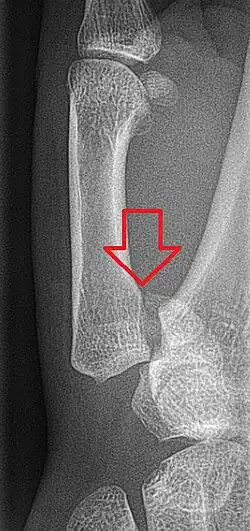

Bennett's fracture or Bennett fracture is a type of partial broken finger involving the base of the thumb, and extends into the carpometacarpal (CMC) joint.[1]

This intra-articular fracture is the most common type of fracture of the thumb, and is nearly always accompanied by some degree of subluxation or frank dislocation of the carpometacarpal joint.

Though these fractures commonly appear quite subtle or even inconsequential on radiographs, they can result in severe long-term dysfunction of the hand if left untreated. In his original description of this type of fracture in 1882, Bennett stressed the need for early diagnosis and treatment in order to prevent loss of function of the thumb CMC joint, which is critical to the overall function of the hand.[4]

- In the most minor cases of Bennett fracture, there may be only small avulsion fractures, relatively little joint instability, and minimal subluxation of the CMC joint (less than 1 mm). In such cases, closed reduction followed by immobilization in a thumb spica cast and serial radiography may be all that is required for effective treatment.[5]